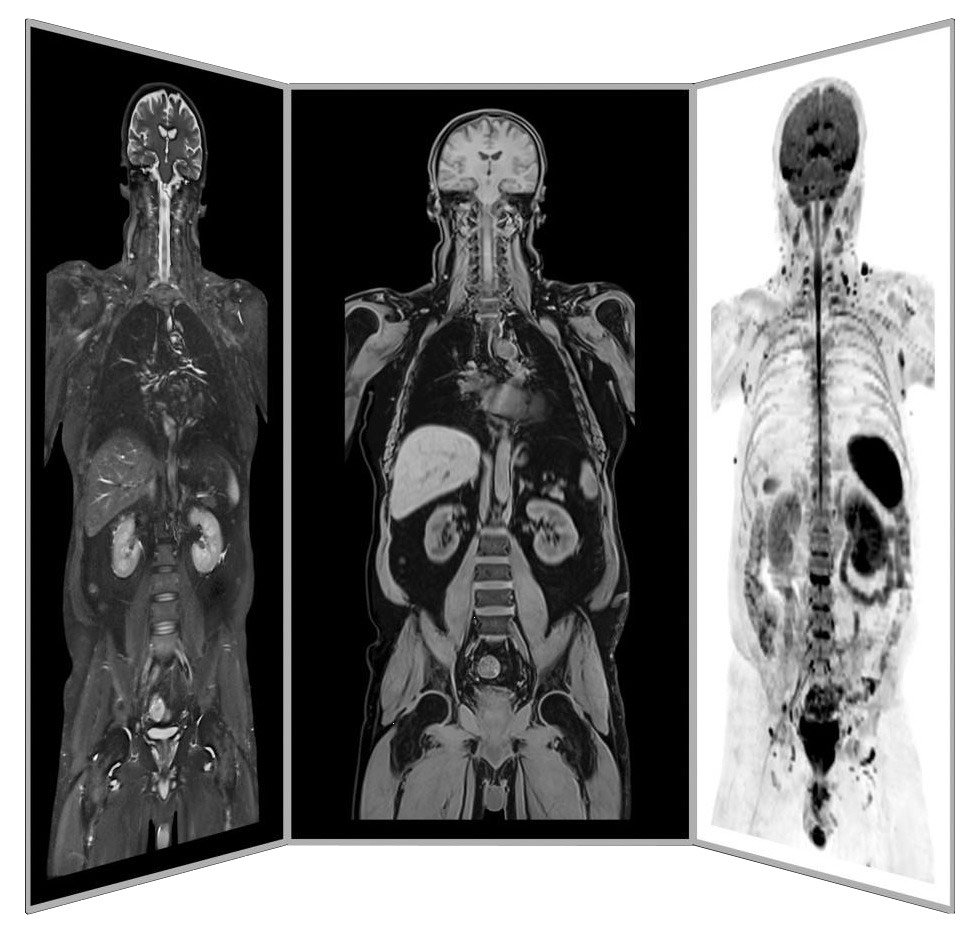

Precision MRI scans - find the source of pain

ANOVA IRM © Siemens Healthcare GmbH